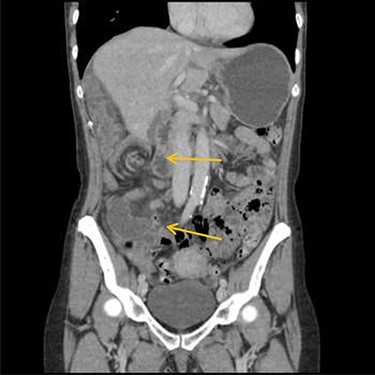

Emergency diagnostic laparoscopy was performed and findings were: 180 degree volvulus of terminal ileum, cecum and ascending colon overlapped each other and overriding the right loop of the liver, the lateral attachment of the right colon was long dilated and floppy (Figs 5 and 6). The dudeno-jejenal flexure was malrotated and lying in left upper quadrant just below to splenic flexure. Three congenital bands were found tilted around the terminal ileum, cecum and base of the appendix. Turbid free fluids with no evidence of infection also noted in the right upper quadrant and right para-colic gutter (Fig. 7). Otherwise, bowels were found healthy and viable. A healthy retrocecal and subserosal appendix was also noted intraoperatively. We converted to open Laparotomy and proceeded with right hemicolectomy due to complex intraoperative findings. The postoperative period was uneventful, and patient was discharged at home on postoperative Day 7.

Showing floppy dilated cecum ileum and ascending colon twisted around the liver and mesentery.